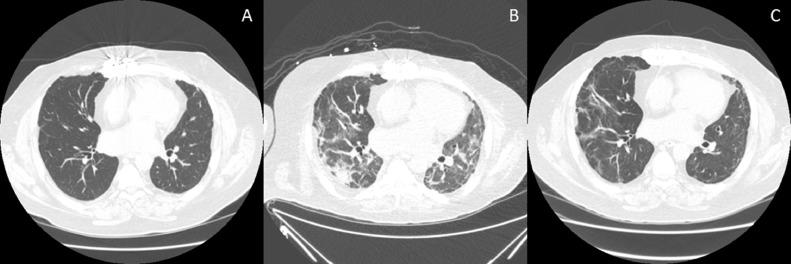

As compared to RSV, patients with COVID-19 were more likely to present with constitutional symptoms, spirometric decline, pulmonary opacities, new or worsening respiratory failure, and need for ventilator support. Patients with SARS-CoV-2 infection were less likely to receive a multimodality treatment strategy, and they experienced worse post-infection lung function loss, functional decline, and three-month survival. A significant proportion of patients with COVID-19 needed readmission for worsening allograft function (36.4%), and chronic kidney disease at initial presentation was associated with this complication. Lower pre-morbid FEV appeared to increase the risk of new or worsening respiratory failure, which was associated with worse outcomes. Overall hospital survival was 88% (n = 22). Follow-up data was available for all discharged patients (median: 43.5 days, range 15-287 days). A majority had persistent radiological opacities (19/22, 86.4%), with nearly half of the patients with available post-COVID-19 spirometry showing > 10% loss in lung function (6/13, median loss: 14.5%, range 10%-31%).

与 RSV 相比,COVID-19 患者更有可能出现全身症状、肺功能下降、肺部阴影、新发或加重呼吸衰竭以及需要呼吸机支持。SARS-CoV-2 感染患者不太可能接受多模式治疗策略,并且感染后肺功能下降、功能下降和三个月生存率更差。相当一部分 COVID-19 患者需要因移植物功能恶化而再次入院(36.4%),初始表现时慢性肾脏病与这种并发症有关。较低的术前 FEV 似乎增加了新发或加重呼吸衰竭的风险,而这与更差的结果相关。总体医院生存率为 88%(n=22)。所有出院患者均有随访数据(中位随访时间:43.5 天,范围 15-287 天)。大多数患者存在持续的影像学阴影(19/22,86.4%),在可获得 COVID-19 后肺功能检查的患者中,近一半患者的肺功能丧失超过 10%(6/13,中位丧失:14.5%,范围 10%-31%)。